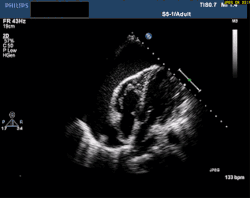

At the bedside, point-of-care echocardiography should be used.[22] This is non-invasive and can help diagnose the four types of shock.[24] Echocardiography can look for ventricular dysfunction, effusions, or valve dysfunction.[3][25] Measurement of the vena cava during the breathing cycle can help assess volume status.[22][24] A point-of-care echocardiogram can also assess for causes of obstructive shock. The vena cava would be dilated due to the obstruction. In pulmonary embolism, the right ventricle will be dilated. Other findings include paradoxical septal motion or clots in the right heart or pulmonary artery. Echocardiography can assess for pericardial effusion. In tamponade, collapse of the right atrium and ventricle would be seen due to pressure in the pericardial sac.[24]